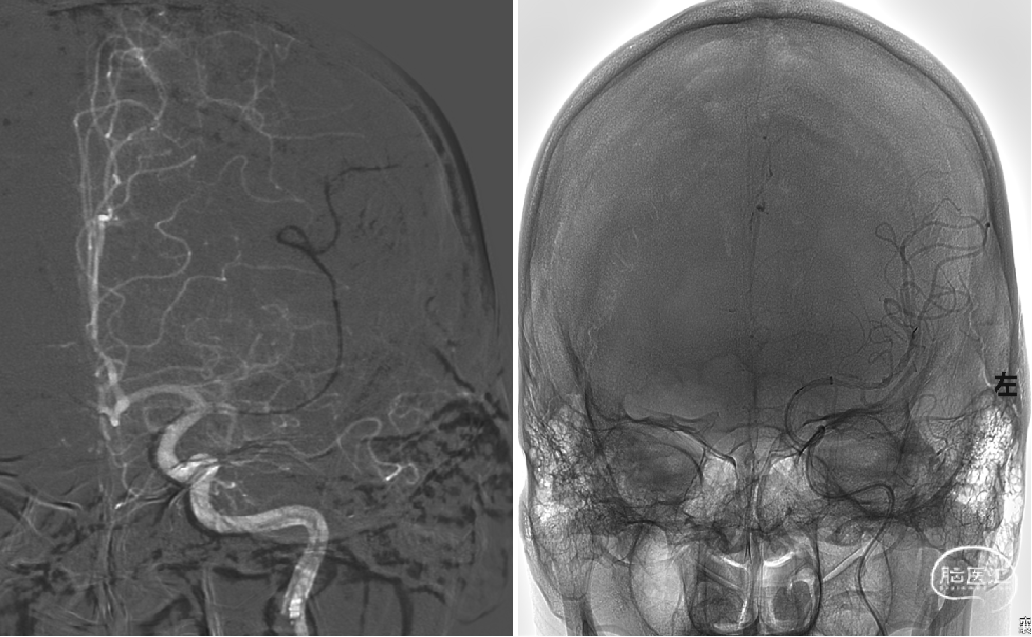

复查造影显示左侧大脑中动脉显影良好,M1段局部毛糙,前向血流:TICI分级:III级,予以替罗非班5ml动脉内缓慢推注,观察15分钟、30分钟分别造影,左侧大脑中动脉显影良好,考虑患者年轻,未放置支架。